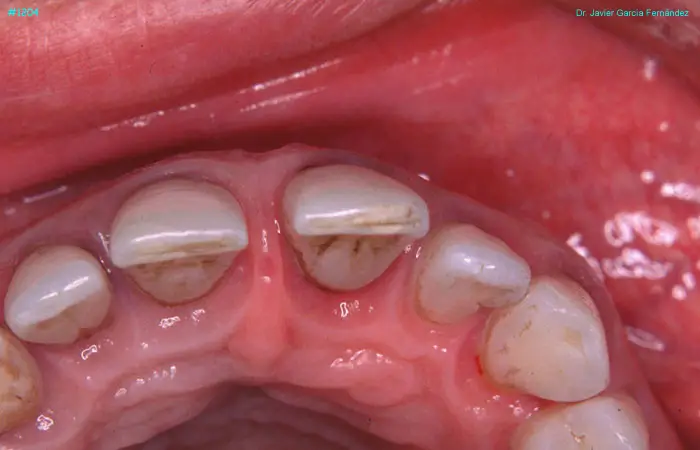

Atlas of Surgical Techniques in Periodontics. Chapter III. Atlas de Técnicas Quirúrgicas en Periodoncia